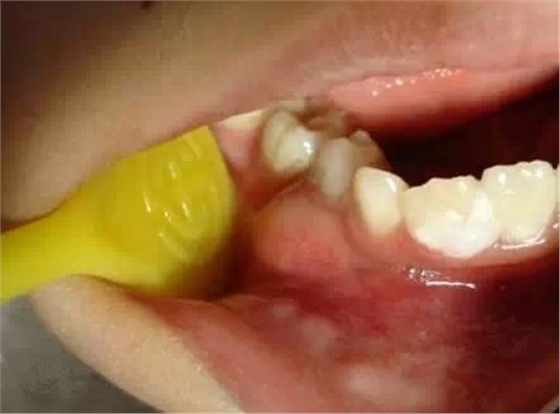

乳牙急性根尖周炎的應(yīng)急處理,首先應(yīng)建立髓腔引流,用快速鋒利的渦輪機(jī)牙鉆開髓,開放髓腔,使炎性滲出物或膿液通過根管引流。 (福建醫(yī)大口腔醫(yī)院 高生輝老師的圖片)

治療步驟:1)去齲、開髓

揭髓室頂

(以上圖片引用自福建醫(yī)大附屬口腔醫(yī)院兒童科 高生輝老師的課件,非常感謝!)